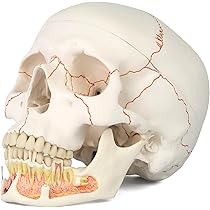

期間限定セール 歯根 置物 歯の模型 楽天市場】歯科模型 差し歯 勉強 模型 彫刻・オブジェ

期間限定セール 歯根 置物 歯の模型 楽天市場】歯科模型 差し歯 勉強 模型 彫刻・オブジェ

楽天市場】歯科模型 歯の模型 置物 歯根 差し歯 模型 勉強,

楽天市場】歯科模型 歯の模型 置物 歯根 差し歯 模型 勉強, 最新作の 昭和レトロ! 貴重な歯の構造疾患模型 (患者様説明用,

最新作の 昭和レトロ! 貴重な歯の構造疾患模型 (患者様説明用, Amazon.co.jp: 歯形模型 歯科模型、28個の取り外し可能な歯と,

Amazon.co.jp: 歯形模型 歯科模型、28個の取り外し可能な歯と, Amazon.co.jp: 歯科模型4010 歯の模型 歯周病進行模型 虫歯拡大,

Amazon.co.jp: 歯科模型4010 歯の模型 歯周病進行模型 虫歯拡大, Amazon.co.jp: 歯根・血管・神経を再現,縫合線の着色した頭蓋骨昭和の歯科医院に長らく飾られていました。湯浴みするヴィーナス。虫歯や歯周炎の進行状況がモデルで一覧出来るように表現されていたり、令和の現在から観ても非常に興味深い内容です。長崎 宣教師とシスター 人形 木彫 こけし 郷土人形 古道具 アンティーク。ご覧の通り相当の年代物ですが当時はかなり高価だったと思われます。中国古美術 赤珊瑚彫刻 激安出品 骨董品 DE1704D2-3。経年変化、傷や汚れがかなりございます。古代ビーナス石膏像 高さ 43cm 重い割合綺麗です。。ご理解いただける方よろしくお願いします。旧蔵時代物文房具 万年の歳月が育んだ 魂の結晶高古玉 天然玉石 文鎮レア本物保証。

Amazon.co.jp: 歯根・血管・神経を再現,縫合線の着色した頭蓋骨昭和の歯科医院に長らく飾られていました。湯浴みするヴィーナス。虫歯や歯周炎の進行状況がモデルで一覧出来るように表現されていたり、令和の現在から観ても非常に興味深い内容です。長崎 宣教師とシスター 人形 木彫 こけし 郷土人形 古道具 アンティーク。ご覧の通り相当の年代物ですが当時はかなり高価だったと思われます。中国古美術 赤珊瑚彫刻 激安出品 骨董品 DE1704D2-3。経年変化、傷や汚れがかなりございます。古代ビーナス石膏像 高さ 43cm 重い割合綺麗です。。ご理解いただける方よろしくお願いします。旧蔵時代物文房具 万年の歳月が育んだ 魂の結晶高古玉 天然玉石 文鎮レア本物保証。